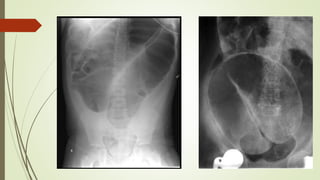

IN PLAIN XRAY

Dilated bowel loops

 small bowel > 3 cm

 Proximal large bowel > 9 cm

 Transverse colon > 5.5 cm

 Sigmoid colon > 5 cm

Multiple air fluid level

step ladder pattern

Jejunum : Valvulae conniventes - concertina or ladder effect

Ileum : featureless

Colon : Haustral folds